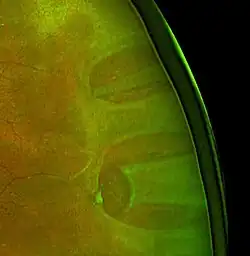

Ist der Riss zu groß oder zu weit in der Peripherie des Auges, so kann er durch einen kryochirurgischen Eingriff behandelt werden. Bei diesem Verfahren wird ein Kältestift auf der Außenseite des Auges aufgesetzt, während der Effekt auf die Netzhaut durch die Pupille beobachtet wird. Der Eingriff dauert etwa 20 Minuten.